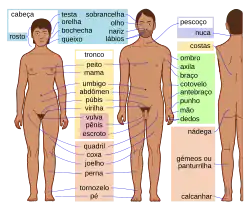

Pénis (português europeu) ou pênis (português brasileiro) humano é o órgão sexual copulatório masculino que também é o responsável pela micção.[1][2] As principais partes são: a raiz (radix); o corpo (corpus); e o epitélio do pénis incluindo o corpo cavernoso e o prepúcio cobrindo a glande.[1] O corpo do pénis é constituído de três colunas de tecidos: dois corpos cavernosos, os dorsais e o corpo esponjoso entre os anteriores no lado ventral. A uretra humana masculina passa através da glândula prostática onde une-se com o ducto ejaculatório através do pénis.[3] A uretra atravessa os corpos esponjosos, e a sua abertura, o meato, dependo do tipo de glande. É a saída excretora para a micção e ejaculação de sémen.[2] A maior parte de desenvolvimento do pénis é composto polo mesmo tecido embrionário que o do clítoris nas mulheres; a pele arredor do pénis e da uretra provém do mesmo tecido embrionário do qual são feitos os lábios menores nas mulheres.[4][5] A ereção[6] é a mudança de estado do pénis, o qual expande-se aumentado de tamanho e ficando teso e duro; isto acontece durante a excitação sexual, porém, também pode ter lugar em situação não-sexuais. A alteração genital mais comum é a circuncisão,[7] a remoção parcial ou total do prepúcio por vários motivos; culturais, religiosos e mais raramente, médicos.[7][8] Há bastante controvérsia acerca da circuncisão.[9]

Partes

- Raiz do pénis (radix): É a parte anexada, consistindo no bulbo do pénis no meio e na crus do pénis, um de cada lado do bulbo. Encontra-se dentro da bolsa perineal superficial.

- Corpo do pénis (corpus): Possui duas superfícies: dorsal (posterossuperior no pénis ereto) e ventral ou uretral (voltado para baixo e para trás no pênis flácido). A superfície ventral é marcada por um sulco na direção lateral.

- O epitélio do pénis consiste na pele da haste, no prepúcio e na mucosa prepucial na parte interna do prepúcio e cobrindo a glande. O epitélio não está preso à haste subjacente, por isso é livre para deslizar de um lado para o outro.[10]